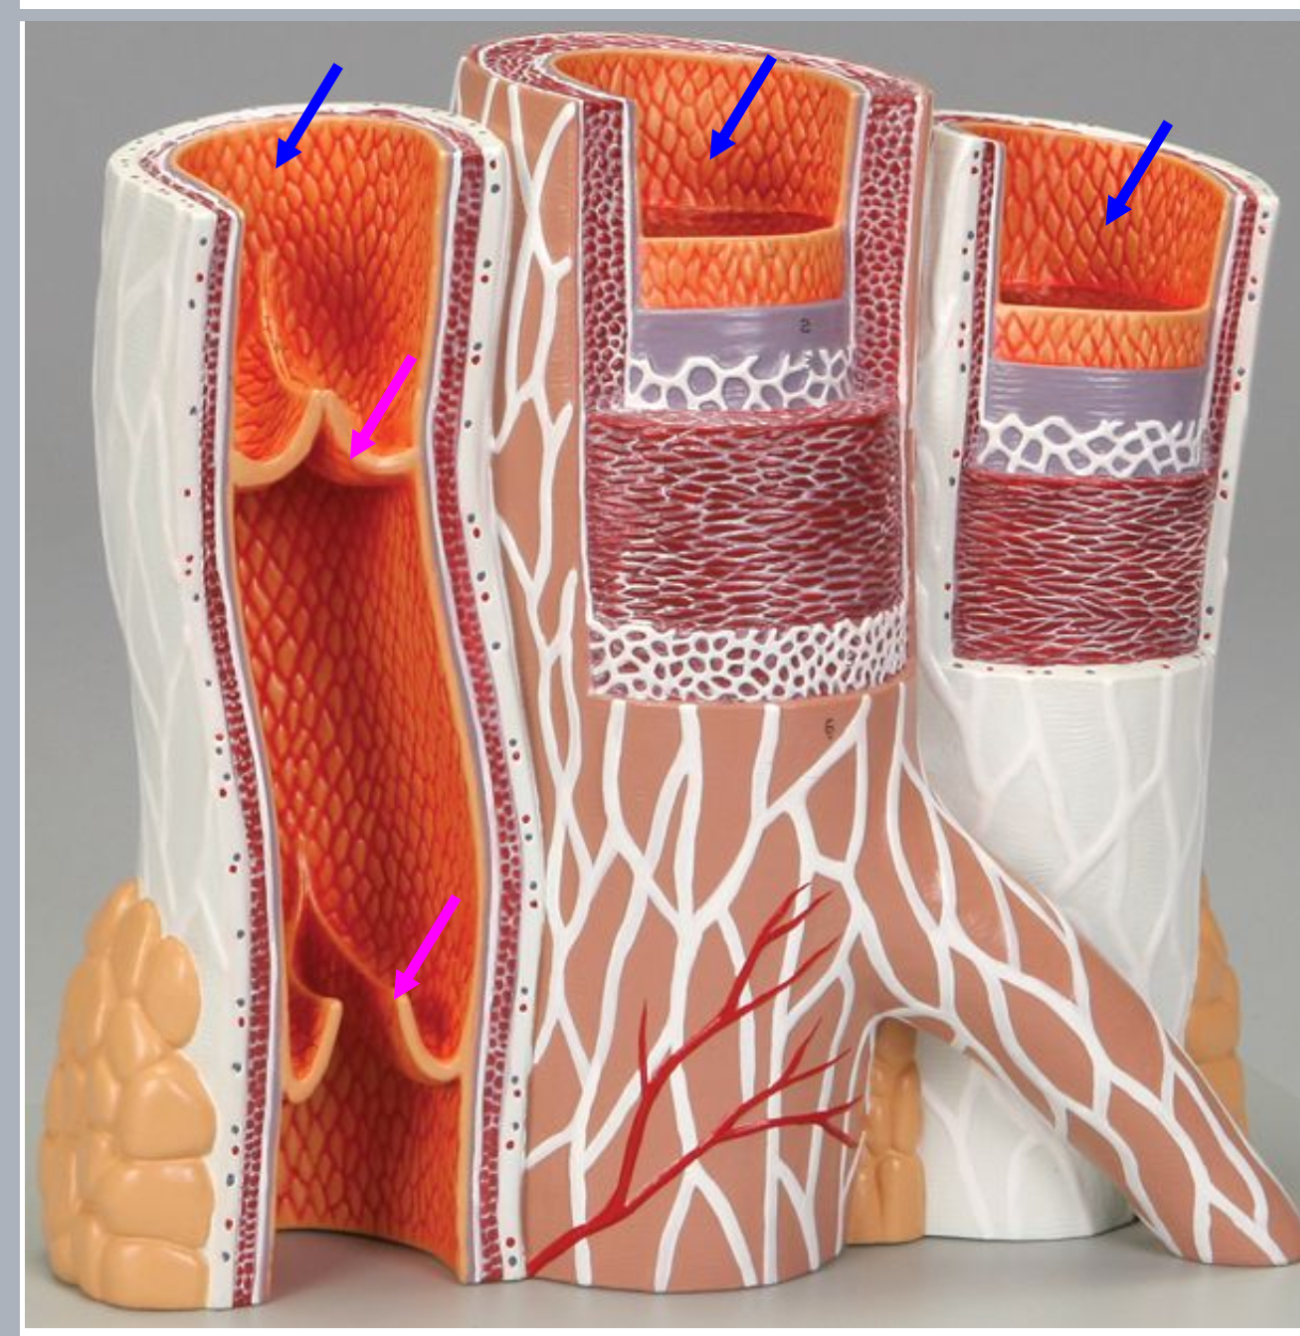

Tunica intima

Name the blue arrow

Lines lumen and release vasoactive chemicals

Function of tunica intima

Venous valves

Name the pink arrow

Prevent backflow of blood

Function of venous valves